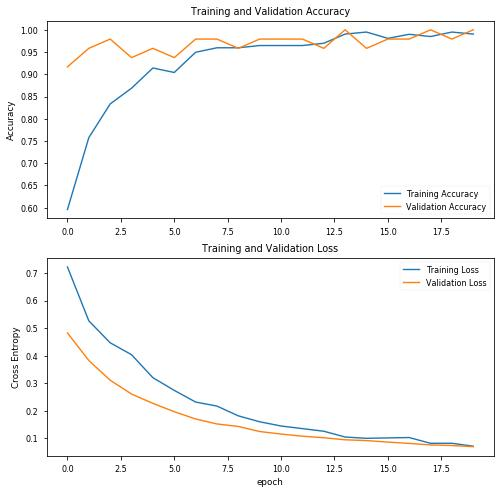

结果看起来已经相当有趣了,验证数据的精度达到了92%!绘制精度图表:

使用20个阶段和初始参数,结果看起来非常有趣,验证数据的精度达到100%!让我们绘制精度图表,评估训练的模型,并查看混淆矩阵:

precision recall f1-score support covid 0.96 1.00 0.98 27 pneumo 1.00 0.96 0.98 27 accuracy 0.98 54 macro avg 0.98 0.98 0.98 54weighted avg 0.98 0.98 0.98 54

混淆矩阵

[[27 0] [ 1 26]]acc: 0.9815sensitivity: 1.0000specificity: 0.9630

通过训练模型(初始选择超参数),我们得到:

- 100%敏感度,也就是说,对于COVID-19阳性(即真正例)的患者,我们可以在100%的概率范围内准确地确定他们为“COVID-19阳性”。

- 96%特异性,也就是说,在没有COVID-19(即真反例)的患者中,我们可以在96%的概率范围内准确地将其识别为“COVID-19阴性”。

结果完全令人满意,因为只有4%的患者没有Covid会被误诊,但与本例一样,肺炎患者和Covid-19患者之间的正确分类是最有益处的,因此我们至少应该对超参数进行一些调整,再次进行训练。